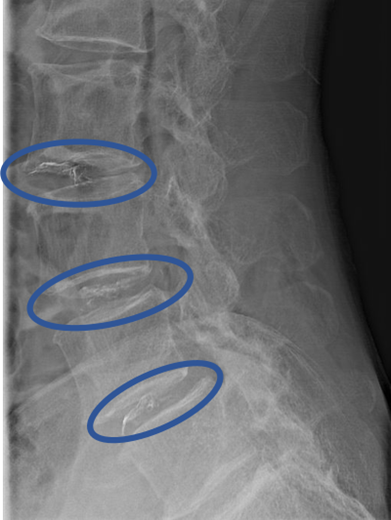

画像及び所見について

L1/2: 椎間板変性症

L2/3: 椎間板変性症、繊維輪断裂

L3/4:椎間板変性症、椎間板ヘルニア

L4/5: 椎間板変性症、椎間板ヘルニア、繊維輪断裂

L5/S:椎間板変性症

以上の事が画像上認められます。

L2/3、3/4、4/5 に

椎間板変性症、椎間板ヘルニア、繊維輪断裂 を認め、主症状の原因の可能性が高い。